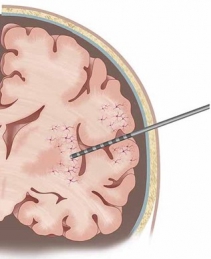

In addition to the very valuable iEEG recordings from the clinical macroelectrodes, our iEEG recordings also include signals recorded with microelectrodes. The additional microelectrodes have a diameter of about 40 μm (smaller than the hair) and spread out of the tip of the clinical intracranial electrode. They are added solely for research purposes and, because of their small size, they can record the electrophysiological firing activity generated by nearby individual neurons. We analyze this data by using algorithms which classify the different waveforms recorded by a single microwire into action potentials generated by different neurons. We also use population decoding methods to extract the information associated by the neurons (e.g. “concept” neurons which preferably fire in response to specific images of the same individual). To localize the site of the macro- and micro-electrodes with high spatial resolution, we combine post-implantation CT scans with pre-implantation neuroimaging scans from the 7-Tesla MRI, available at the University of Magdeburg.

4. © Carlson et al., 2018. Reproduced according to the terms of Creative Commons Attribution License. Carlson, April A., Ueli Rutishauser, and Adam N. Mamelak. 2018. “Safety and Utility of Hybrid Depth Electrodes for Seizure Localization and Single-Unit Neuronal Recording.” Stereotactic and Functional Neurosurgery 96 (5): 311–19. https://doi.org/10.1159/000493548.